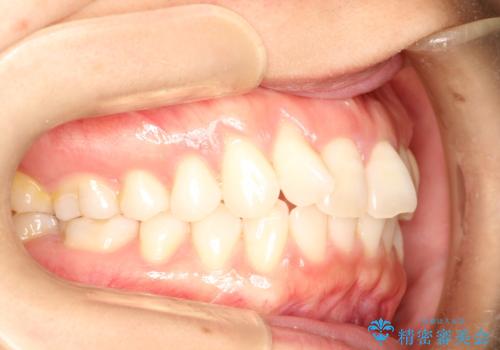

インビザラインによる矯正治療 前歯を整った歯並びへ

- 上の前歯のねじれを気にされて来院されました。

右上の前から2番目の歯が90度近くねじれて並んでいました。

こちらを当初セラミックでの治療をご希望でしたが、セラミック治療の限界と矯正治療のメリットをご説明をさせていただきました。

患者様に考えていただき、矯正治療で前歯をきれいにすることとしました。

インビザラインを使用して矯正することとしました。